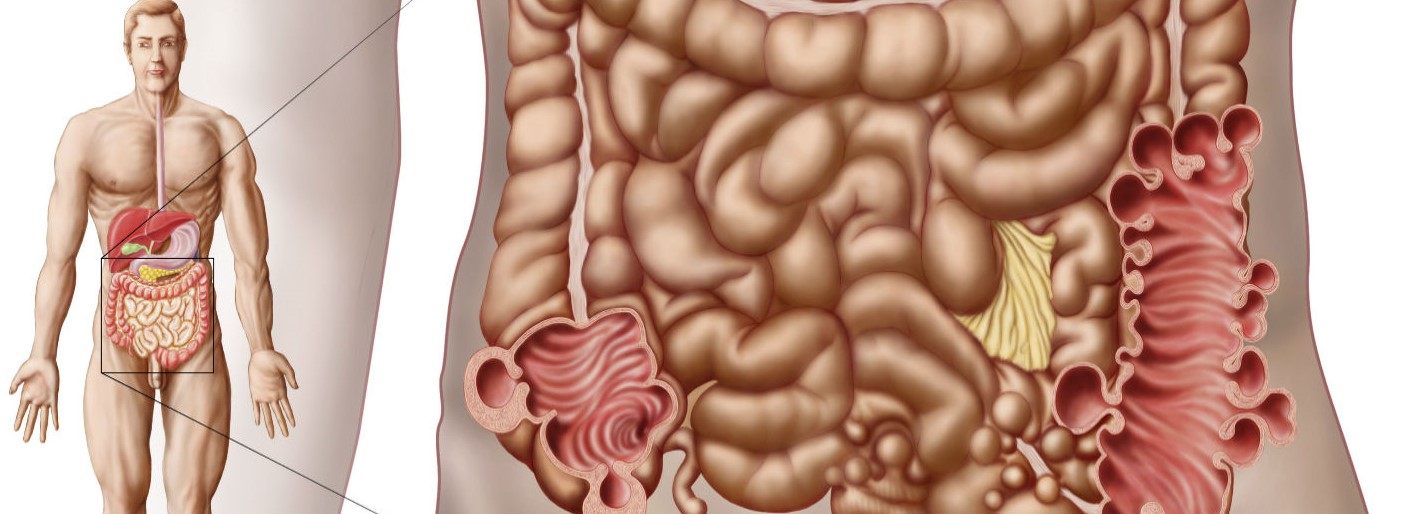

Ο καρκίνος ή ο κακοήθης όγκος, είναι μια ασθένεια στην οποία τα φυσιολογικά κύτταρα μιας δεδομένης περιοχής του σώματος αρχίζουν να αναπτύσσονται ανώμαλα, προσβάλλοντας τους ιστούς και άλλες φορές εξαπλώνονται και σε άλλες περιοχές. Ο πρωκτικός σωλήνας είναι ένας αγωγός μέσω του οποίου το ορθό συνδέεται με το εξωτερικό του σώματος. Ο πρωκτικός καρκίνος εμφανίζεται όταν τα κύτταρα στο δέρμα γύρω από τον πρωκτό αρχίζουν να αναπτύσσονται εκτός ελέγχου.

Αυτή η πολύ σοβαρή ασθένεια μπορεί να προκληθεί σε οποιοδήποτε μέρος ή περιοχή του πρωκτού. Αξίζει να εκτιμηθεί ότι ακριβώς το μέρος όπου ξεκινά ο κακοήθης όγκος καθορίζει τον τύπο του καρκίνου που αντιμετωπίζεται και, ως εκ τούτου, τη θεραπεία του.

- Αφενός, υπάρχει το καρκίνωμα πλακωδών κυττάρων, ο πιο κοινός τύπος καρκίνου του πρωκτού. Προέρχεται από τα κύτταρα που ευθυγραμμίζουν το κανάλι του πρωκτού και εξαπλώνεται στους υποκείμενους ιστούς.

- Αφετέρου, το χλωρογόνο καρκίνωμα, το οποίο είναι αρκετά παρόμοιο με το προηγούμενο. Η αντιμετώπιση και των δύο, στη συντριπτική πλειονότητα των περιπτώσεων, είναι ακριβώς η ίδια.

- Και τέλος, το αδενοκαρκίνωμα, το λιγότερο συχνό από όλα. Προέρχεται από τους αδένες του πρωκτού. Ένα από τα κύρια χαρακτηριστικά του είναι ότι είναι ασυμπτωματικός τύπος όγκου στα αρχικά του στάδια. Έτσι, όταν διαγνωστεί, σχεδόν στο 100% των περιπτώσεων, βρίσκεται σε προχωρημένη φάση.